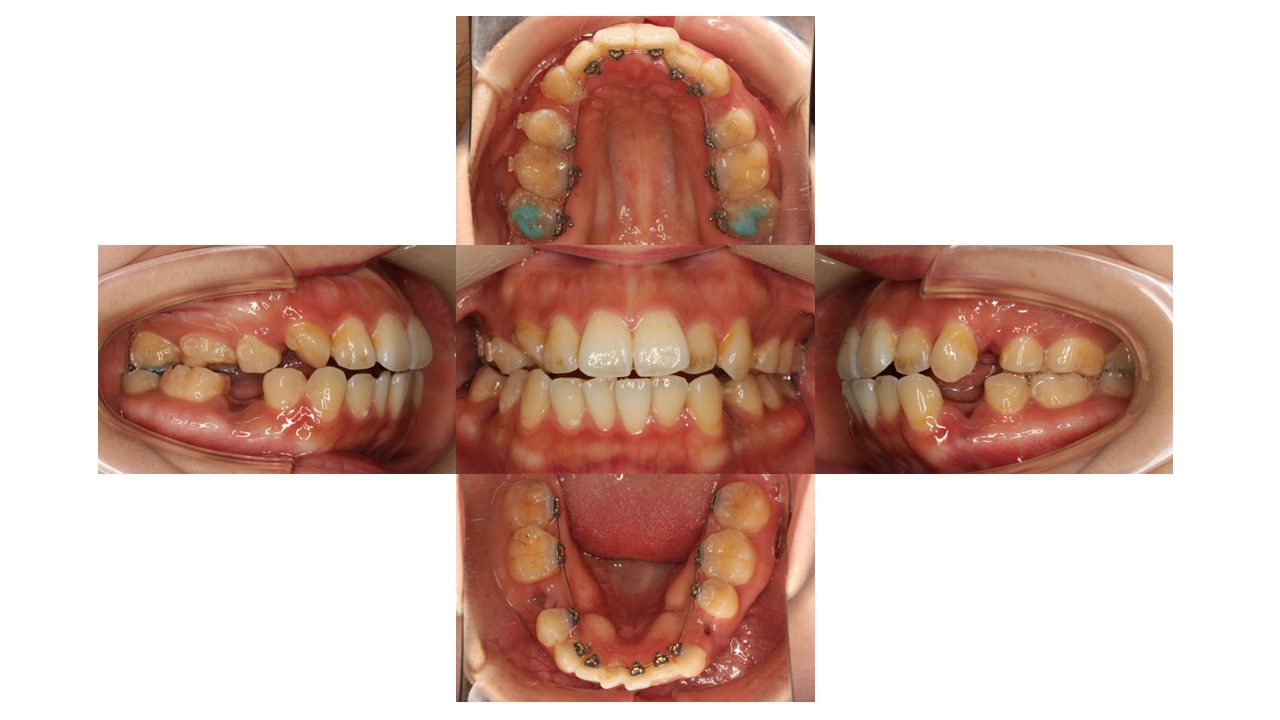

装置装着時の口腔内の状態です。

上顎左右ともに4番目、下顎左が4番目右が5番目を抜歯し、裏側矯正(リンガル)で歯を動かしていきます。

現在の歯並びだと、下の歯が上の歯の装置にぶつかってしまうため、上の奥歯に「バイトアップ」という青い材料をつけてかみ合わせをあげています。